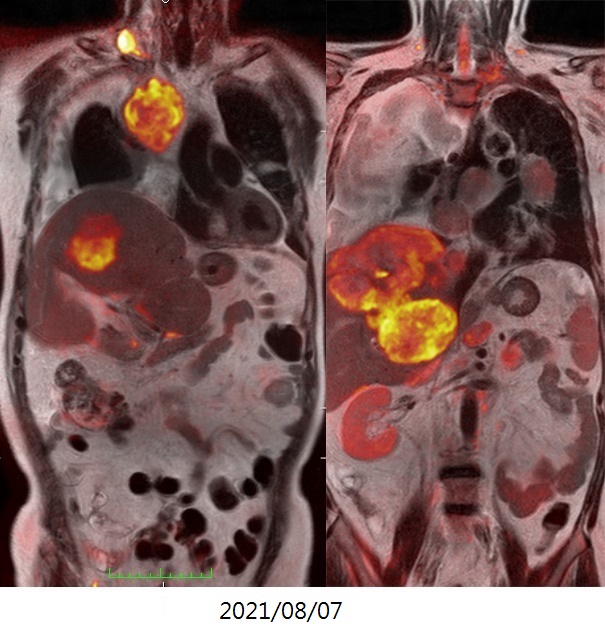

血管內光動脈灌注治療之基因檢查圖像的變化(升結腸癌、多處肺、肝、淋巴結轉移)